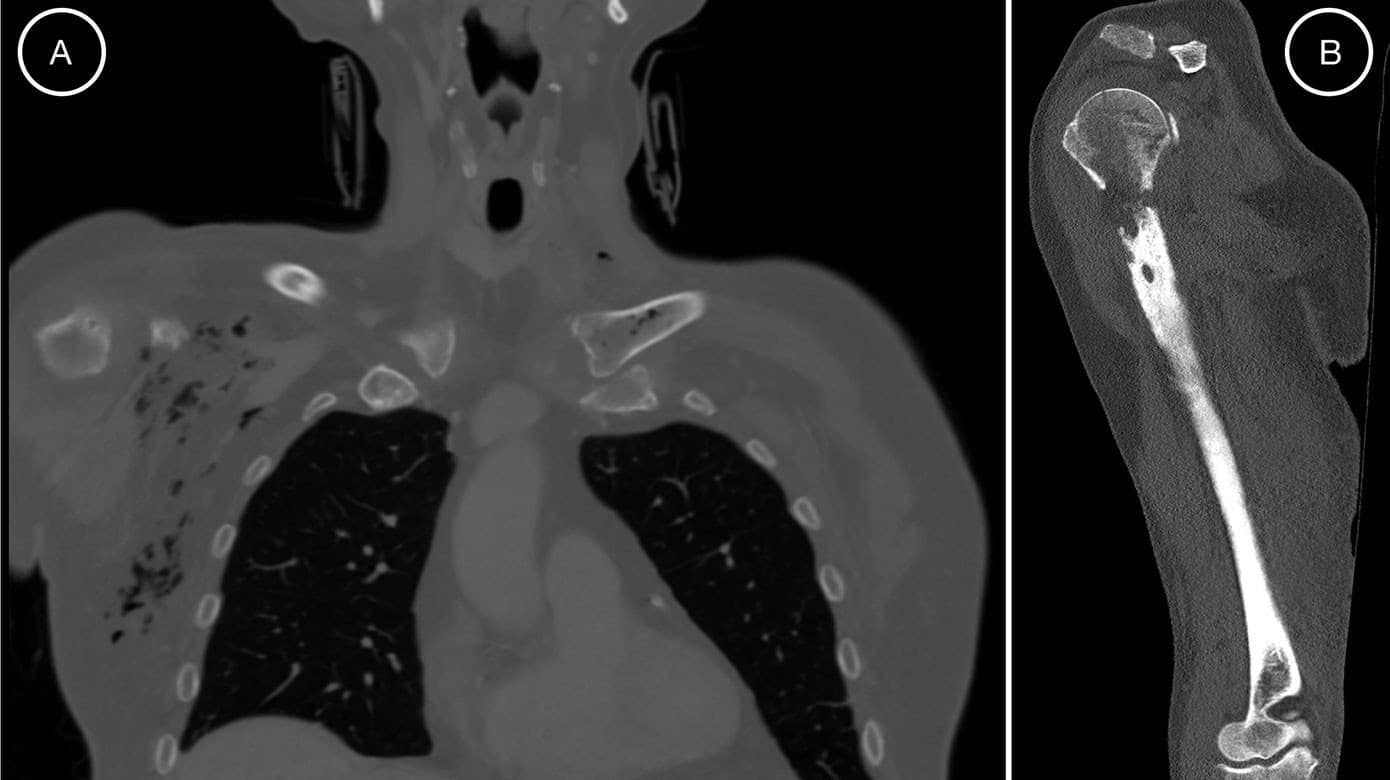

Med tiltagende smerter og nytilkommen hævelse af højre overekstremitet viste en fornyet CT en nytilkommen ossøs destruktion med luftudvikling i højre humerus og omkringliggende muskler og fascier samt luftudvikling i venstre mediale klavikelende (Figur 1A). Disse fund var forenelige med EO.

Efter tre måneder uden antibiotika blev patienten genindlagt med recidiv af osteomyelitis (Figur 1B) og udviklede en absces i højre overarm. Dyrkninger af materiale fra UL-vejledt drænage viste K. pneumoniae med uændret resistensmønster. Patienten fik herefter i.v. antibiotika i tre måneder med god effekt.